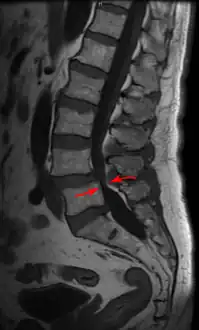

- MRI of a lumbar spinal stenosis L4-L5. L4-L5 antherolisthesis of grade I. Hypertrophy of interspinous ligaments in relation to Baastrup's disease.